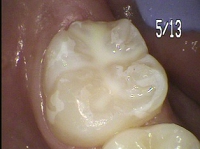

6才臼歯(第一大臼歯)には、必ずシーラントをおすすめしています。

シーラントは、歯の溝に樹脂を詰めてむし歯から予防する処置です。

シーラント術前